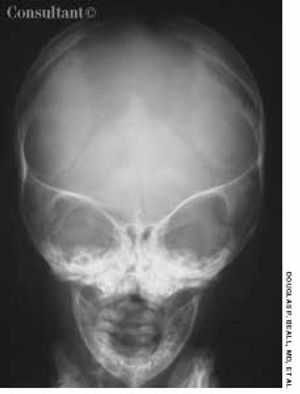

During his last routine pediatric visit, a 4-month-old boy with a large head circumference (98th percentile for his age) was referred for radiographic evaluation. The infant had been delivered by cesarean birth because of cephalopelvic disproportion; his head size had gradually increased since birth. There was a family history of this condition.